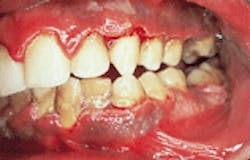

Case 1

Acute necrotizing ulcerative gingivitis (ANUG)

1. Identify the predisposing factor(s) for ANUG.

a. decreased resistance to infection

b. heavy smoking

c. poor oral hygiene

d. increased stress

e. all of the above

2. Identify the origin of ANUG.

a. viral

b. bacterial

c. fungal

d. parasitic

e. autoimmune

3. Identify which of the following is NOT a feature of ANUG.

a. tissue fibrosis

b. tissue sloughing

c. necrotic interdental papillae

d. erythematous gingiva

e. pain and bleeding

4. Identify the TRUE statement(s) concerning ANUG.

a. occurs in persons aged 15-35

b. occurs with fever and lymphadenopathy

c. affects mandibular anterior gingiva

d. characterized by a rapid onset

CASE 1: 1 = e; 2 = b; 3 = a; 4 = e